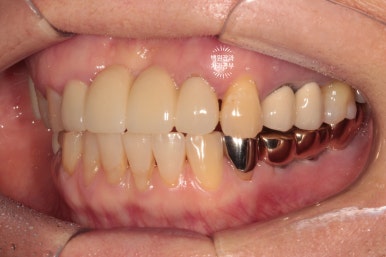

그런게 기가막힌건 그냥 입 안 사진을 봐서는 그렇게 안좋아보이지 않는다는 것입니다..

수술 전의 사진과 비교해서 생각보다 임플란트가 원래 자리와 비슷한 레벨에 위치해 있음을 확인할 수 있습니다.

정면에서 보았을 때는 잘 보이시지 않을 수 있으나,

측면에서 보았을 때, 처음에 저희 병원에 내원하셨을 때에 비해 많이 길어지지 않고 비슷한 길이의 크라운으로 제작된 것을 확인하실 수 있을겁니다.

수술 전에 비해 약 1-2mm 정도 임플란트 크라운이 길어진 느낌이네요.

좌측은 깔끔하게 마무리된 지르코니아 브릿지를 보실 수 있네요 :)